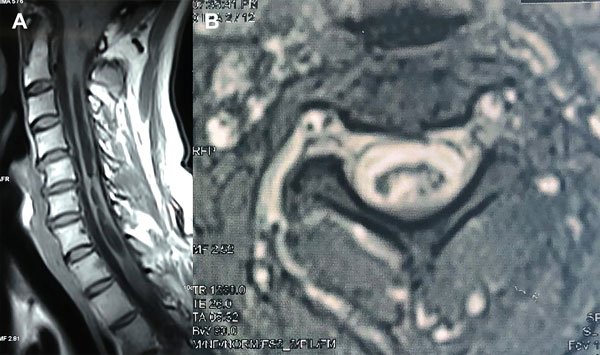

Un varón de 38 años de edad consultó por haber padecido una cérvico braquialgia derecha 30 días antes. En el momento de la consulta sus síntomas habían desaparecido y el examen neurológico fue normal. La RM mostró discopatías cervicales múltiples con una dilatación quística en la médula cervical a nivel C5-C6 que no tomaba el contraste con gadolinio (Figura 6A). Para profundizar el diagnóstico diferencial se realizó una RM en contraste de fase para medir la velocidad del LCR a nivel del canal cervical. La velocidad medida fue de 11 cm/seg (Figura 6B-C). Se hizo el diagnóstico de SM espinal primaria causada por una discopatía cervical a nivel C5-C6. Como el paciente estaba asintomático sólo se indicó control periódico. En su última evaluación, 2 años después, la situación clínica e imagenológica no había cambiado por lo que se mantuvo la misma conducta.

Figura 6: Caso 4. A: RM de columna cervical en plano sagital ponderada en T2 que muestra una cavidad intramedular entre C5 y C6 compatible con siringomielia. B: Estudio de dinámica de LCR que muestra una imagen de magnitud en fase anterógrada con señal hiperintensa el flujo en sístole con disminución del pasaje del LCR en C5-C6. C: Estudio de dinámica de LCR que muestra una imagen de magnitud en fase retrógrada con señal hipointensa el flujo en diástole con la alteración del pasaje de LCR a nivel C5-C6.